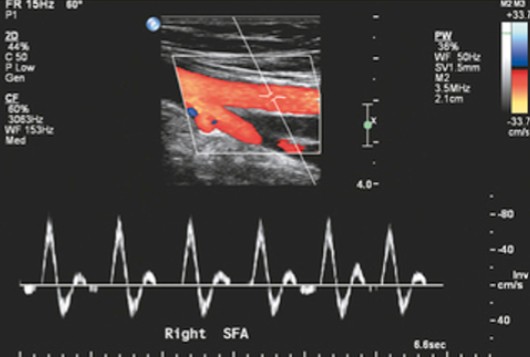

What lower extremity arteries are examined with continuous wave doppler exams? (6)

SFA

What kind of exam is being performed here?

Continuous wave doppler

What exam is being performed here?

CW Doppler Exam